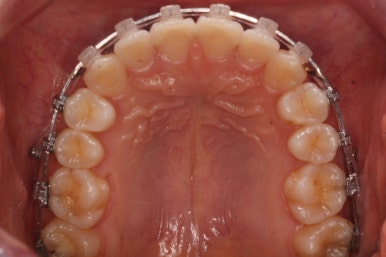

우선 윗니부터 가지런하게 합니다. 그리고 아랫니는 가지런하게 할 준비를 하죠.

점점 치열이 가지런해지고 있습니다.

이제 치열은 거의 가지런해졌습니다.

치열이 가지런해졌다는 뜻은 이제 곧 뒤로 당기기가 가능해졌다는 뜻이기도 합니다.

우선 윗니가 먼저 가지런해졌기 때문에 윗니부터 뒤로 당기기 시작합니다.